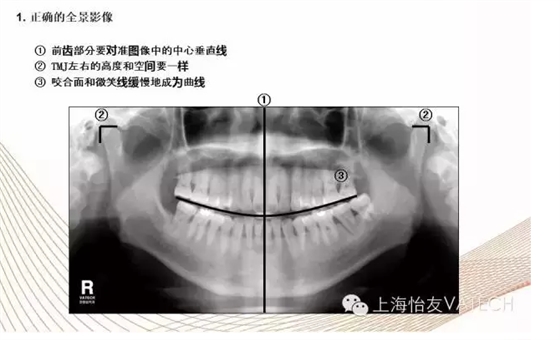

首頁口腔影像 全景拍攝程序

全景拍攝程序